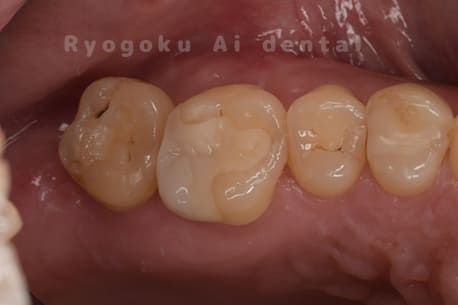

Case03

- 重度カリエス、慢性根尖性歯周炎

- 治療内容

- 自家歯牙移植

- 治療費用

- 220,000円

他院で右下の根の治療を行い、セラミックを被せる説明をされていたが、根の治療が終わらないため転院された患者さんです。隣の親知らずの抜歯の必要性と、根の治療を行なっている歯牙の予後が悪いため、移植治療を提案し、右下の親知らずの抜歯と同時に、右下の奥歯(7番)への移植治療を行いました。被せ物を行う必要もなく、順調に経過してます。

<リスク・副作用>

治療後、痛みや違和感、出血、腫れなどが出る事があります。喫煙者、糖尿病などの方の場合、歯が生着しない場合があります。